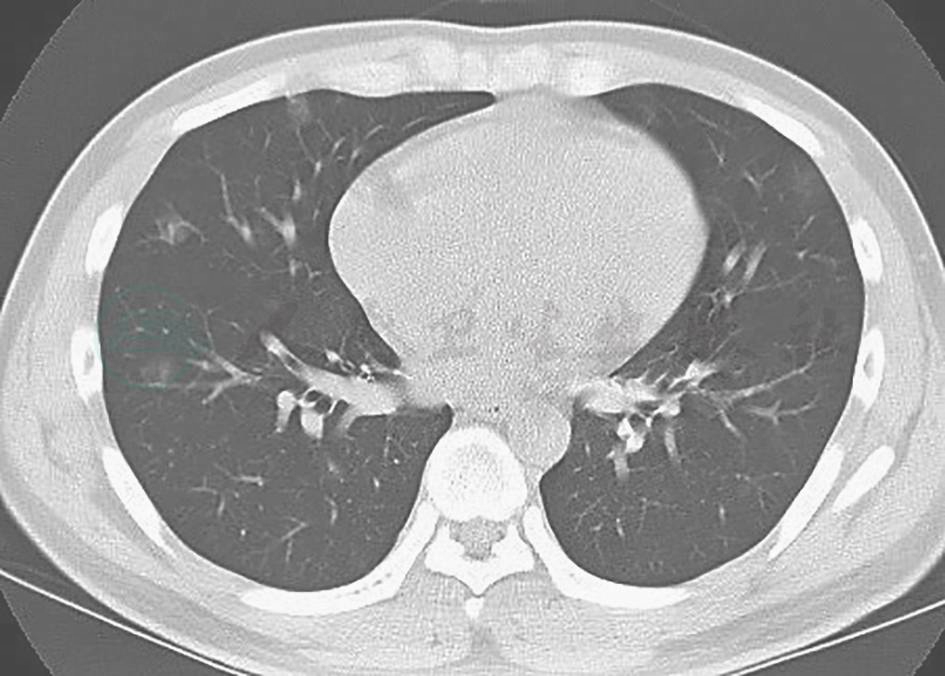

真菌感染:本例患者外观消瘦,曾在外院接受广谱抗生素治疗,需注意念珠菌二重感染可能(念珠菌性肺炎可表现为肺实变影),需积极寻找病原学依据以助鉴别。另外,曲霉菌感染常继发于免疫功能低下的情况,病情进展迅速且凶险,其典型胸部影像学表现为晕征和新月征(图2),与本例患者情况不符,可基本排除。

图2 肺曲霉菌病胸部影像学表现

胸部CT可见右上肺肿块样高密度影,伴支气管充气征